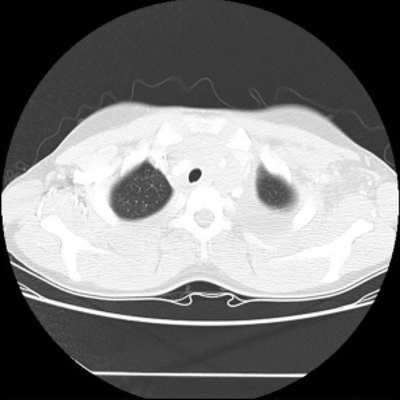

We now consider applying the proposed image registration method on real lung CT images retrieved from the National Lung Screening Trial (NLST) dataset [1]. Fig. 9(a) and Fig. 9(b) show two slices of lung CT images that we use as the source and the target (see Fig. 9(c) for the absolute intensity difference). We remark that the CT images are originally with different intensity, and so we apply an intensity histogram matching before running the registration experiment. Fig. 9(d) shows the registration result obtained by our proposed method. It can be observed that our method successfully produces a large deformation on the right lung of the source image to match that of the target image (see also Fig. 9(e) for the final absolute intensity difference). On the contrary, DDemons [47] (Fig. 9(f)), LDDMM [5] (Fig. 9(g)), Elastix [29] (Fig. 9(h)) and DROP [18] (Fig. 9(i)) all fail to produce an accurate and bijective registration result. This shows that our method is more capable of handling large deformation image registration.